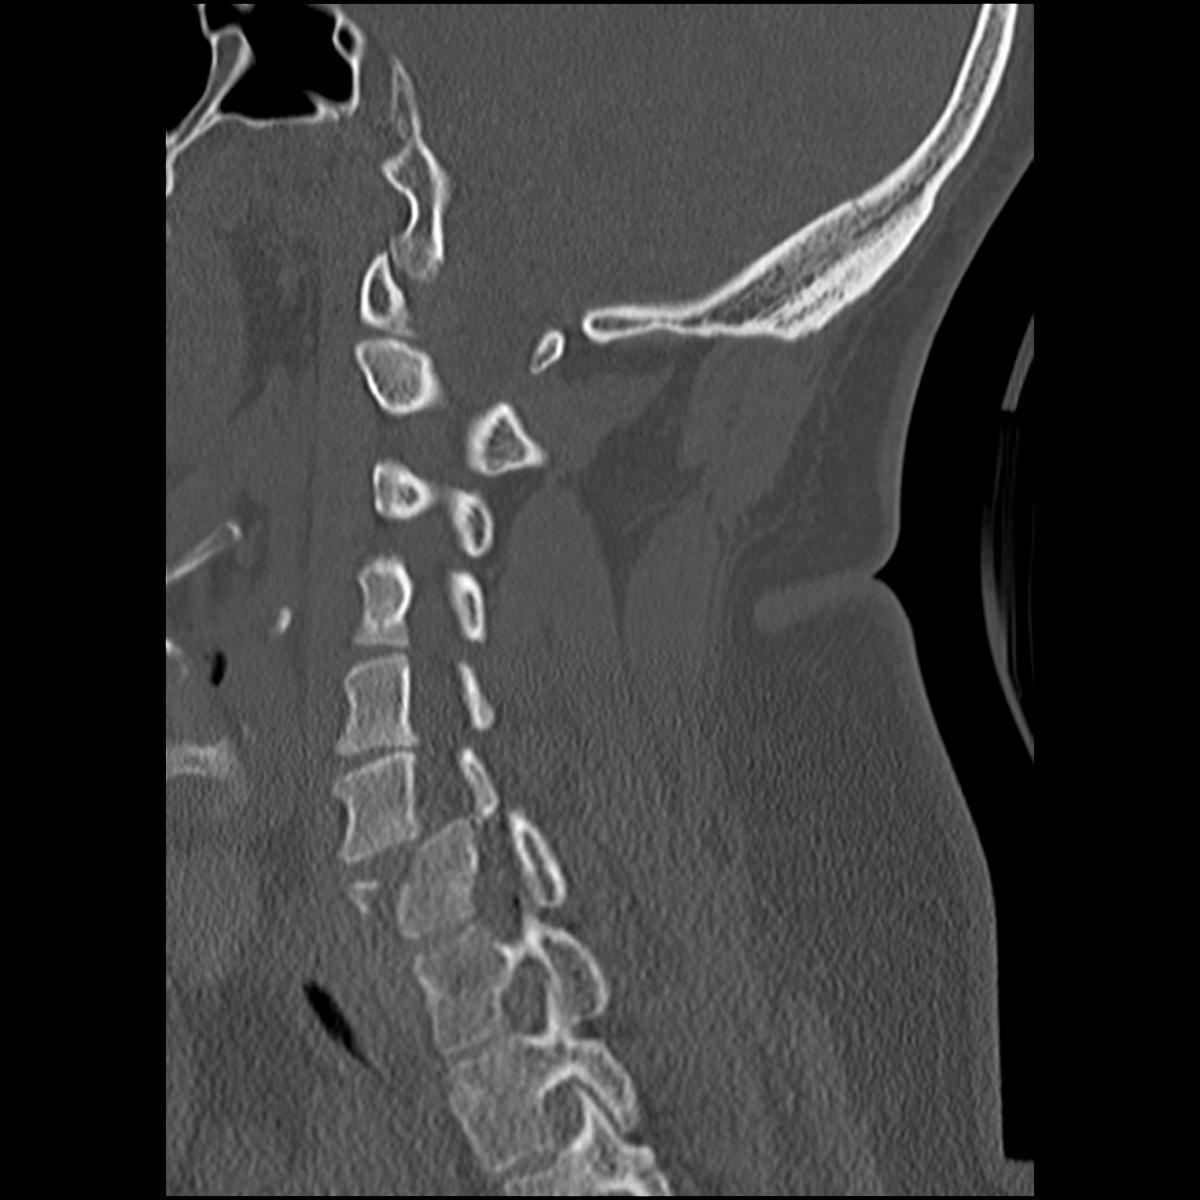

Andrew Dixon, Radiopaedia.org. From the case rID: 31837

Radiologiquement se traduit par :

- Antélisthésis > 3 mm

- Angulation des plateaux vertébraux > à 15°

- Baillement des articulaires postérieures (perte du parallélisme des surfaces articulaires postérieures et subluxation)

- Rupture de l’alignement du mur vertébral postérieur

- Ecart inter-épineux anormal